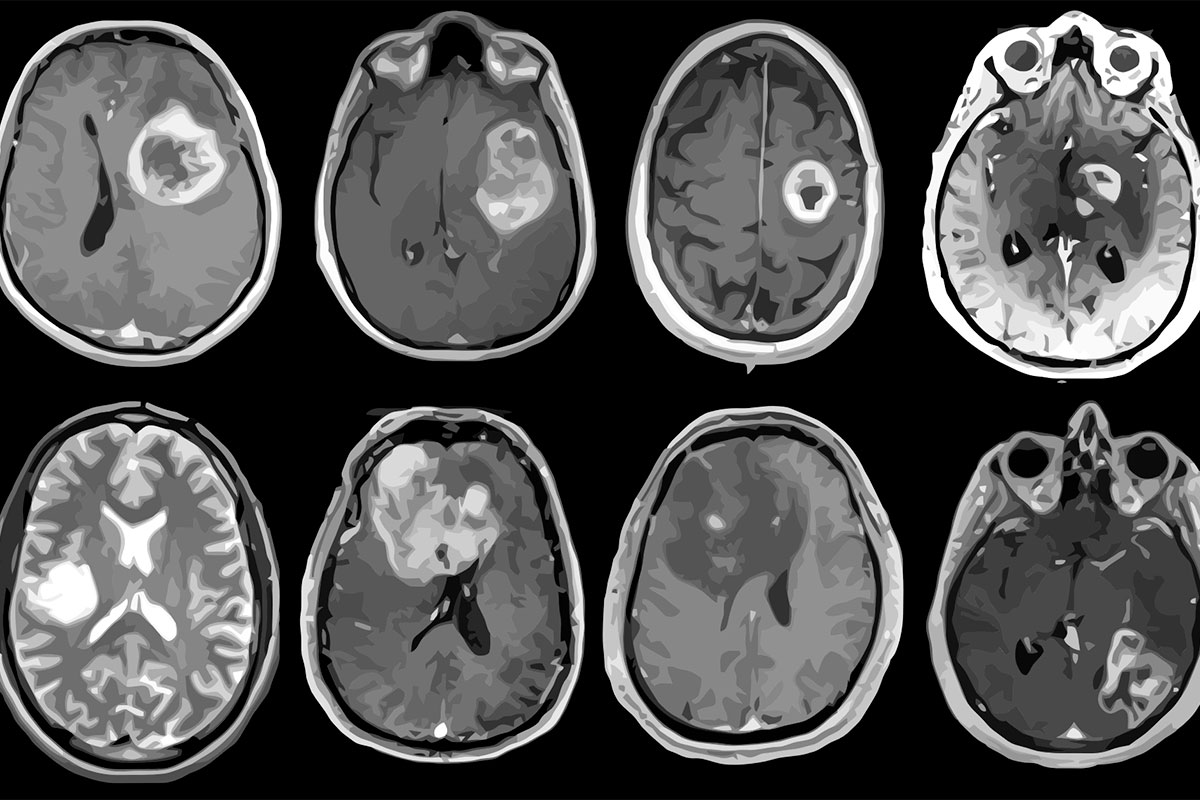

The study, in JAMA Network Open, looked at cancer records from 1992 to 2018 for 3.8 million people in the U.S. They checked cases of cancer that spread to other parts of the body. They compared Generation X to older groups like Baby Boomers and the Silent Generation. The study found that some cancers, like colon, rectal, thyroid, ovarian, and prostate cancers, are getting more common even though medicine is getting better.

Rosenberg and Adalberto Miranda-Filho think more people in Generation X will get certain cancers. Thyroid, kidney, rectum, and colon cancers will go up. Women will have more pancreatic, ovarian, and endometrial cancers. Men will get more prostate cancers and leukemia. Lung cancer will go down for everyone. Men will see fewer liver and gallbladder cancers. Women will have less cervical cancer.